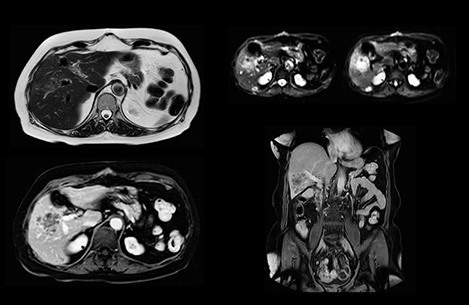

In this example the image quality of the MultiVane XD images is evidently better than in the images without MultiVane XD. Ingenia 1.5T with dS Torso coil solution.

“Our liver exams are quite fast,” says Dr. Baumann. “If the patient tolerates it, we use an arms-up position to reduce the FOV and speed up the exam with dS SENSE.” “We acquire one transversal high resolution T2-weighted sequence with 3 mm slice thickness, for example for pancreas or liver lesions. Then we also add a T2 fat suppressed MultiVane XD SPIR sequence. We perform these two routinely in our liver imaging. We use high dS SENSE factors to significantly shorten scan times to 2-4 minutes, which can improve our protocol; it’s a very robust scan.” “We include mDIXON for the dynamic sequences because of the robust and homogeneous fat suppression we get with that. We had been using eTHRIVE, but we are now quite happy with mDIXON. Sometimes we use a medication to calm the bowels, to further improve the image quality.”